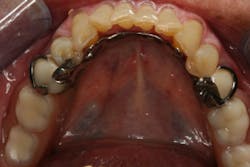

In this case, the diagnostic wax-up of the mounted models gave the technician the new position of the upper incisal edge. The technician then set the maxillary teeth appropriately using models and additional photographs. At the same time, tooth No. 20 was restored, but the lab technician kept the crown and lower partial to predictably create the lower occlusal plane and easily articulate this with the upper immediate denture (figure 18). Note the improved curve of Spee in Figures 19 and 20. Upon completion of the prosthesis, treatment was completed as outlined and the results made the patient feel very comfortable functionally, esthetically, and phonetically.

Figure 18

There was some fine-tuning to the patient's occlusion during the healing period. Nevertheless, the goals of treatment were accomplished very predictably. Figures 21 (horizontal position) and 22 (vertical position) verify both the new vertical and horizontal positions of the upper incisal edge.